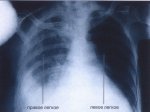

ЛимфогранулематозЛимфогранулематоз — тяжелое общее заболевание, протекающее с опухолевидными разрастаниями лимфатических... ЛимфогранулематозЛимфогранулематоз — тяжелое общее заболевание, протекающее с опухолевидными разрастаниями лимфатических...